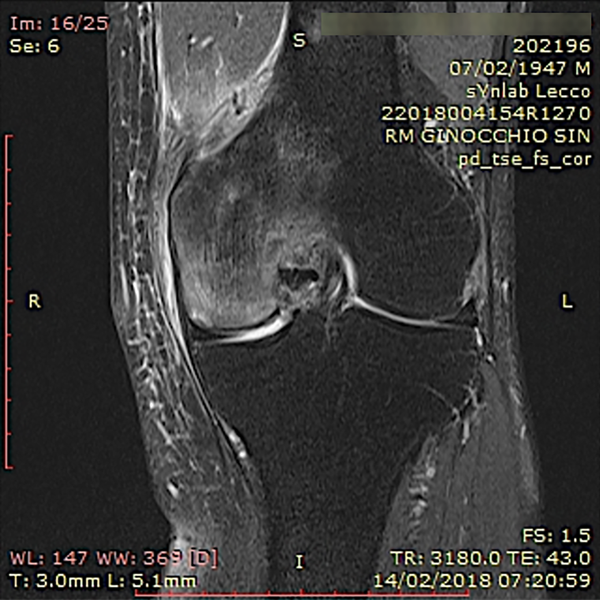

Un estudio clínico reciente concluye que el aumento biológico del hueso subcondral mediante esta técnica resultó en una reducción significativa del dolor y una mejor función articular con resonancia magnética que muestra la resolución de las LMO a los seis y doce meses de seguimiento (figs. 7 a 10).

Figura 7: Un ejemplo de lesión del hueso subcondral en el cóndilo femoral medial de la rodilla tratada con osteocoreplastia. Pretratamiento, vista coronal de la resonancia magnética de la rodilla.

Figura 8: Un ejemplo de caso de lesión del hueso subcondral en el cóndilo femoral medial de la rodilla tratada con osteocoreplastia. Pretratamiento, vista sagital de la resonancia magnética de la rodilla.